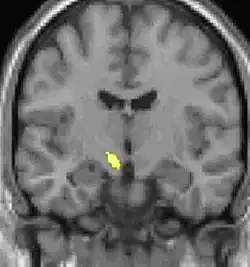

Voxel-based morphometry shows brain area structural differences.

Positron emission tomography (PET) scans indicate the brain areas which are activated during attack only, compared to pain free periods. These pictures show brain areas that are active during pain in yellow/orange color (called "pain matrix"). The area in the center (in all three views) is activated only during cluster headaches. The bottom row voxel-based morphometry shows structural brain differences between individuals with and without CH; only a portion of the hypothalamus is different.[36]